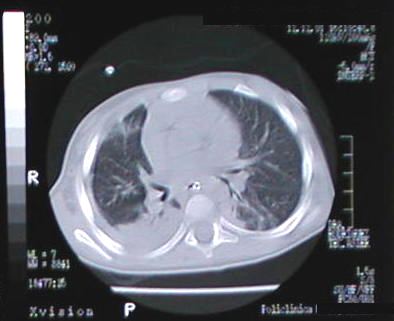

Corte Tomográfico " 2 "

Corte 2 cm por debajo al anterior:

Areas neumonicas bilaterales y el engrosamiento pleural derecho por paqui-pleuritis.